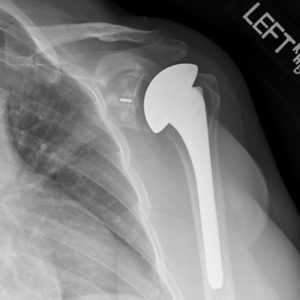

- Однополюсное. Производится имплантация либо лопаточной впадины, либо костной головки.

Для однополюсного эндопротезирования используются гемипротезы, то есть заменяющие только одну часть сустава. По способу установки делятся на поверхностные и штыревые (внедряются в кость).

Рентген после эндопротезирования плечевого сустава